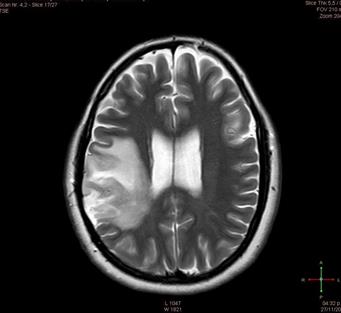

Para los casos seleccionados se documentan estudios de tomografía axial computarizada (TAC) así como de resonancias magnéticas (RM), que fueron realizados a los y las pacientes para poder confirmar el diagnóstico de neoplasia cerebral.

Sujeto 1: mujer de 36 años de edad, diestra, laboraba como dependiente en un negocio y se encontraba desempleada. Acude al Servicio de Neurocirugía del Hospital México con historia de un mes de evolución de deterioro cognitivo y funcional, caracterizado por cefaleas de predominio occipital, alteraciones en su memoria, trastorno de la marcha y tremor distal en extremidades de predominio derecho. Se documentan crisis convulsivas recurrentes, trastornos visuales y refiere visión borrosa. La figura 1 muestra los resultados de la Resonancia Magnética y la tabla 2 presenta el resumen de sus puntuaciones.